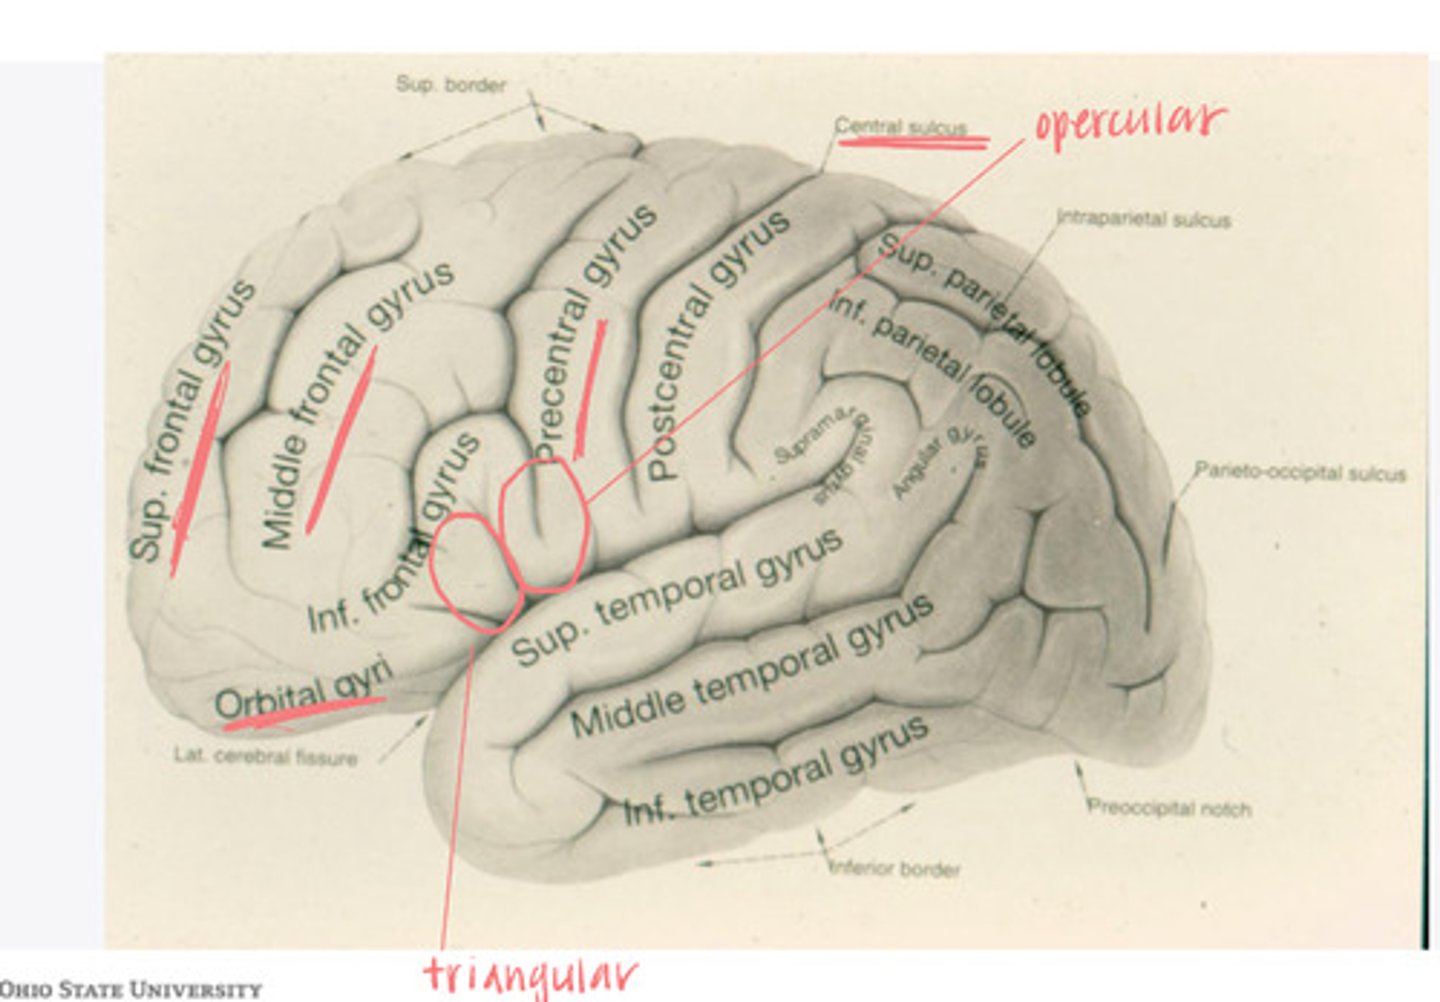

The frontal lobe is divided into what 4 gyri?

-opercular

-triangular

-orbital gyrus

What are the 3 divisions of the inferior frontal gyrus?

-post-central gyrus

-superior parietal lobule

-inferior parietal lobule

What are the divisions of the parietal lobe?

-supramarginal gyrus

-angular gyrus

What are the divisions of the inferior parietal lobule?

-superior temporal

-inferior temporal

What are the 2 major sulci of the temporal lobe (on lateral view)?

-superior temporal

-middle temporal

-inferior temporal

What are the 3 major gyri of the temporal lobe (on lateral view)?